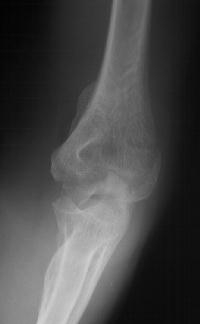

She began immediate protected motion and discontinued splint use at two weeks, despite recommendations to the contrary. These films are two months postop:

Click for larger image

Lateral column not yet fully consolidated on Xray, but clinically healed.